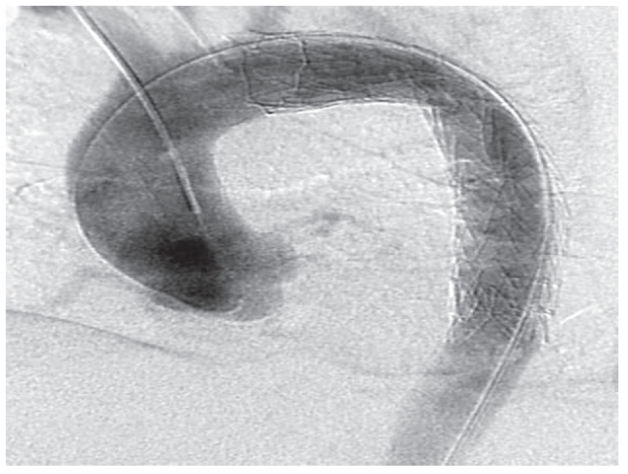

An arch angiogram showed the proximal entry tear into the false lumen (Figure 2). The right femoral artery was explored and a single thoracic stent-graft measuring 37 mm by 15 cm (Gore Tag®, WL Gore and Associates, Inc., Flagstaff, Arizona, USA) was successfully deployed in the descending thoracic aorta to seal off the entry tear, without covering the ostium of the left subclavian artery (Figure 3). The stent-graft was oversized by 15% for the thoracic aortic diameter. Repeat angiogram showed that the entry tear was closed and the right renal artery remained patent and perfused by the false lumen with flow entering into the re-entry site within the right EIA. Two further stents were placed in the right EIA to seal off the exit site of dissection. However, the dissection flap was torn proximally into the distal abdominal aorta with persistent flow into the false lumen perfusing the right kidney. A decision was made to leave and monitor the re-entry tear with serial CT scans. The right femoral artery was closed and a drain was placed in the groin wound for three days.

Figure 2.

Arch angiogram showing the proximal entry tear into the false lumen (arrow).